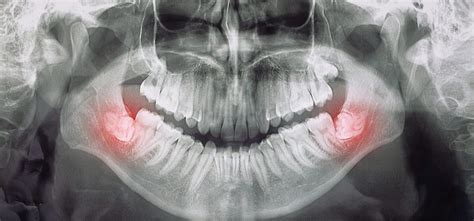

Protiniai dantys yra treti krūminiai dantys, kurių yra 4 - po vieną kiekviename kampe. Jie išdygsta paskutiniai iš visų dantų, todėl tuo metu burnos ertmėje (žandikaulyje) būna likę mažai vietos. Šie dantys vadinami protiniais, nes jie išdygsta, kai asmuo jau būna suaugęs.

Kada yra rekomenduojamas protinių dantų šalinimas?

Protiniai dantys ne visada turi būti šalinami. Jie šalinami tuomet, kai kelia sveikatos problemas. Šie dantys išauga paskutiniai, todėl dažnai jiems nebelieka vietos kur dygti, todėl jie gali įstrigti dantenose ar pradėti dygti kampu. Protinio danties rovimas gali būti rekomenduojamas tik padarius rentgeno nuotraukas, kad būtų įvertinta dantų padėtis ir žandikaulio struktūra, bei protinių dantų įtaka žandikauliui.